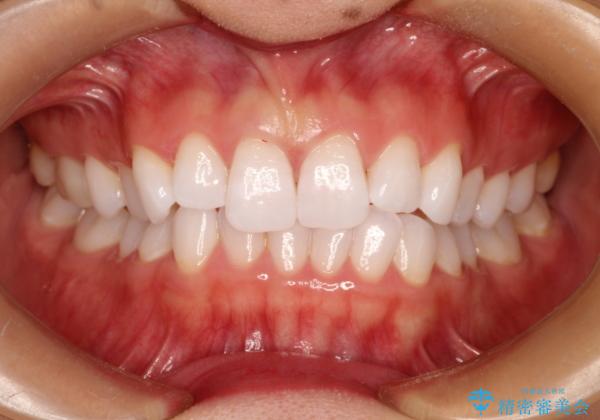

- 前歯の傾きと、ガタガタが気になるとのことで来院されました。

アスリートの方でしたので、競技に支障が少ないインビザラインで治療することとなりました。

前歯の傾きや高さをシミュレーションで患者様と確認しながら、歯並びを仕上げていきました。

遠方での合宿などで長期に来院できない場合も、インビザラインなら治療が可能となります。